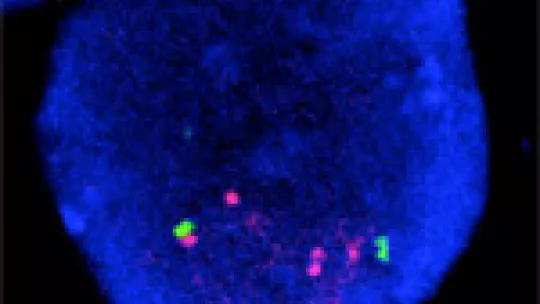

Through experiments using metastatic cells from patients and animal models, the researchers have discovered that Her2 not only accelerates cell division but also evades these cell arrest systems. Her2 stimulates the production of the protein Lip, which deactivates the mechanisms that prevent cell division mediated by TGF-β and the senescence mediated by OIS, thereby leading to accelerated division. “Lip is the baddie in the film. It affects TGF-β and OIS function, both tumour suppression mechanisms”, explains Gomis.